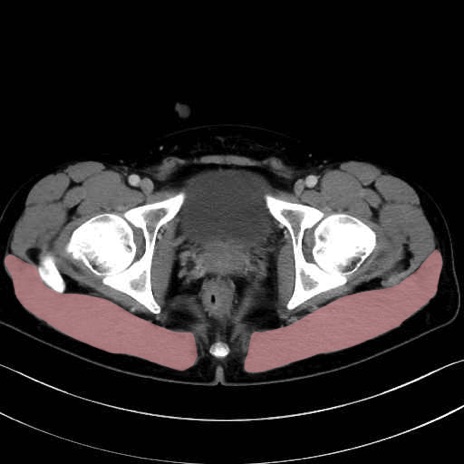

大殿筋 (Gluteus maximus)